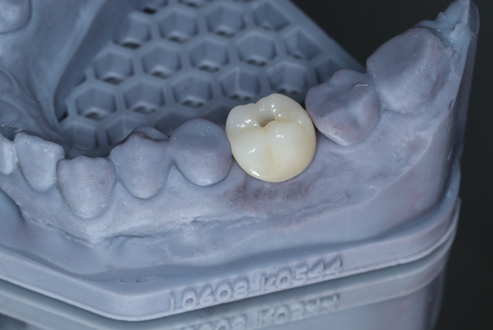

Após 35 dias da cirurgia, a prótese definitiva de zircônia foi instalada com um torque de 10 Ncm, tornando a reabilitação viável em um curto período de tempo e deixando a paciente satisfeita, tanto com a questão estética quanto funcional do implante, e pronta para retornar ao seu país de origem.